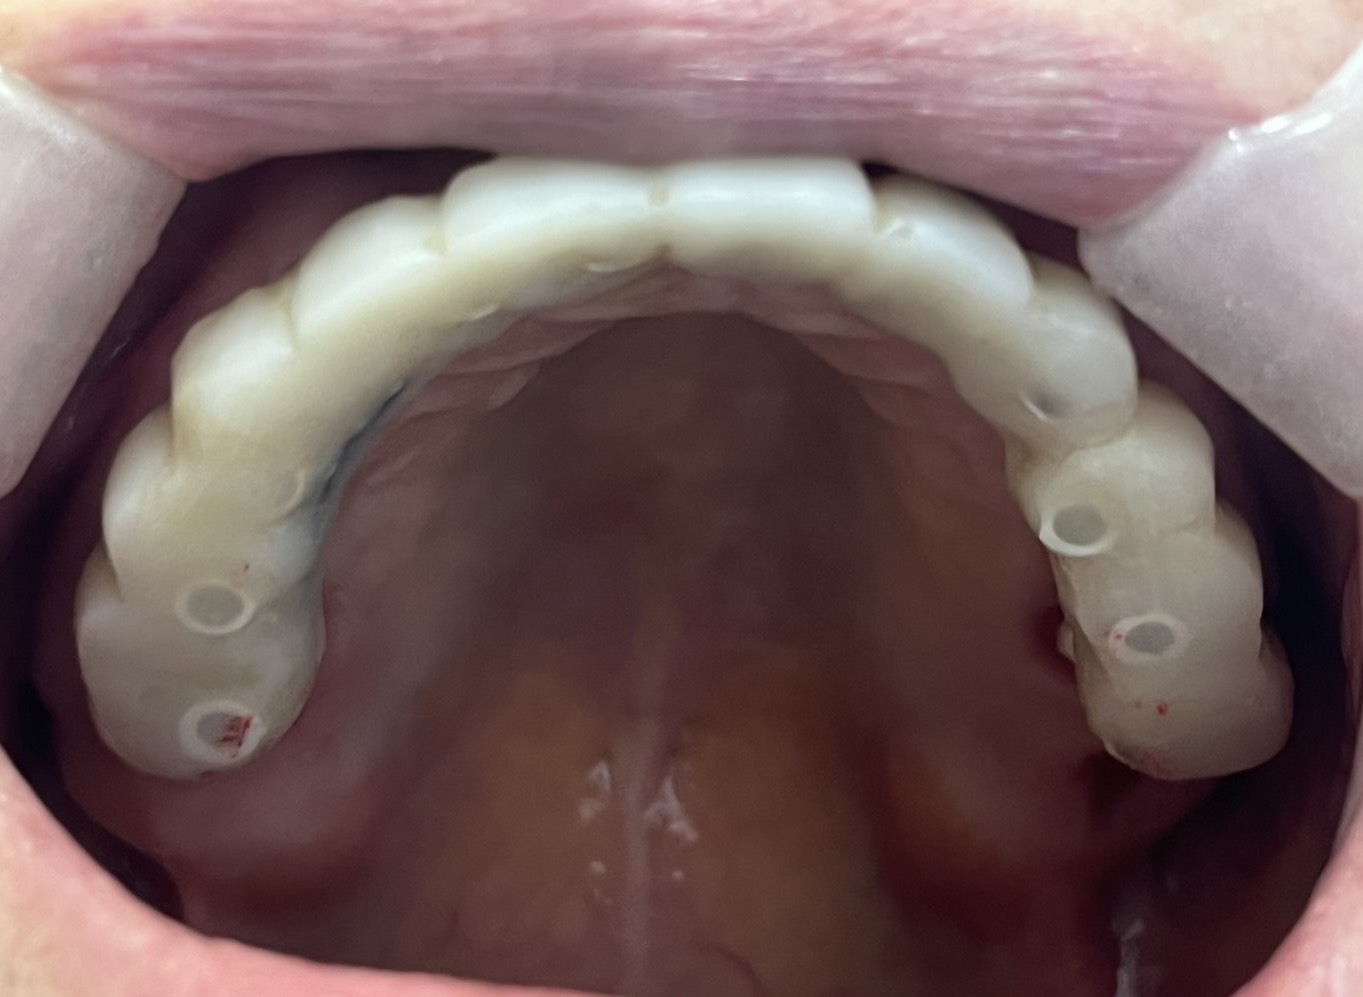

一位患者特地從外州飛到拉斯維加斯,評估後當天決定進行全口植牙。整個療程不到兩小時,即拔即植即固定臨時牙。

手術當天完成全口掃描,四個月後更換為最終固定假牙。這段期間,患者維持良好的生活品質,醫師也能安心照護,不用每天提心吊膽、接不完病患來電。